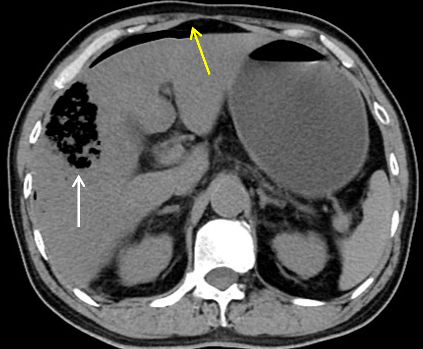

1 病例资料患者,男性,61岁,1 d前(2020-10-9 10点左右)因“无明显诱因出现持续性腹痛”,至外院急诊就诊,腹部CT提示无明显急诊征象(图 1)。实验室检查:白细胞7.25×109/L,中性粒细胞比率75.5%,淋巴细胞比率19.3%,生化提示天门冬氨酸氨基转移酶108 U/L,淀粉酶103 U/L,肌酐73 µmol/L,C-反应蛋白2.4 mg/L,给予解痉、消炎、止痛等对症治疗后出现呕吐、畏寒发热,体温最高超39℃,降温后回家,仍有腹痛、呼吸急促,自行服用三九胃泰。

| 图 1 患者全腹部CT平扫未见明显急诊征象 |